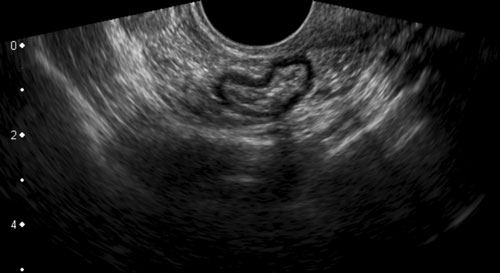

Các hình ảnh thuộc về một bệnh nhân DIE với hình thái tử cung và buồng trứng bình thường.

DIE có các đặc điểm TVUS điển hình, gần như đặc trưng bệnh lý.

Mặc dù rõ ràng là một bệnh lý phụ khoa, nhưng không hiếm trường hợp bị các bác sĩ phụ khoa bỏ sót trong quá trình thực hiện TVUS.

Lý do là phần lớn bệnh nhân DIE (*) không có các nang lạc nội mạc tử cung điển hình và, như ở bệnh nhân này, có tử cung và buồng trứng bình thường (buồng trứng trái và buồng trứng phải). Hơn nữa, chẩn đoán TVUS của DIE đòi hỏi kiến thức chuyên sâu về hình ảnh siêu âm của ruột và bàng quang bình thường cũng như bệnh lý, kiến thức này có thể còn thiếu ở các bác sĩ phụ khoa.

Các ổ lạc nội mạc tử cung trên bề mặt ngoài của đại tràng ở bốn bệnh nhân khác nhau.

Các ổ lạc nội mạc tử cung (*) trong túi cùng Douglas là các khối đặc, giảm âm, kém mạch máu, khu trú không đối xứng, liên tục với lớp cơ giảm âm phía ngoài của đại tràng.

Lớp dưới niêm mạc tăng âm phía trên và niêm mạc đại tràng thường còn nguyên vẹn. Điều này cũng giải thích tại sao máu trong phân khá hiếm gặp trong DIE.

Bờ ngoài của các khối giảm âm này thường dính chặt vào tử cung và/hoặc cổ tử cung. Thường có thể thấy hình ảnh tua gai hoặc “kéo căng” ở các bờ ngoài.